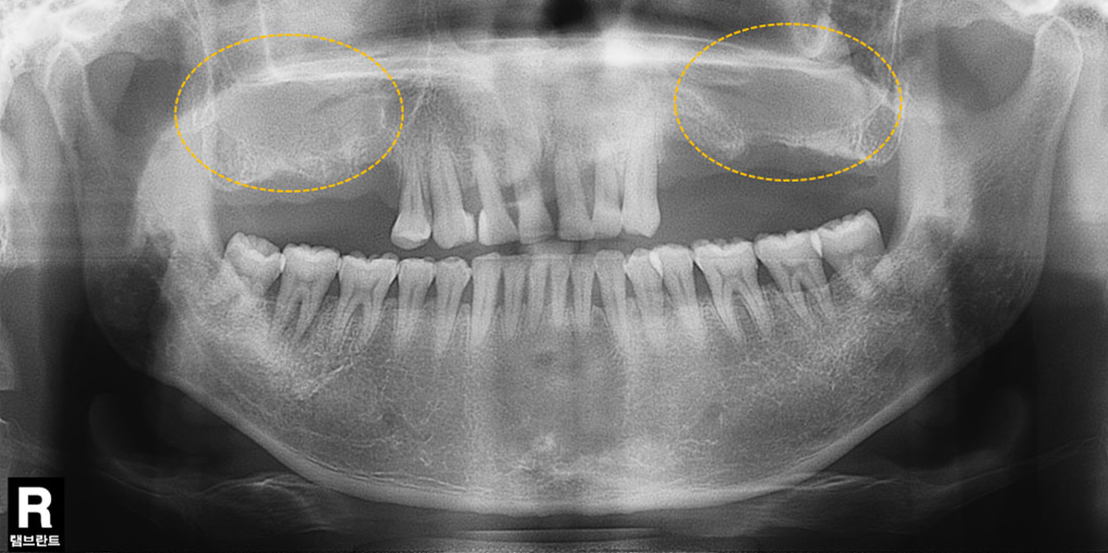

상악동 공간이 내려앉은 경우

윗턱뼈 공기주머니에 뼈이식

치료 전

치료 후